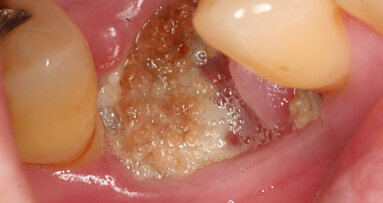

SEOUL, South Korea: Dental implants are a key treatment for tooth loss, but can cause a variety of complications. One such complication is osteonecrosis, ...